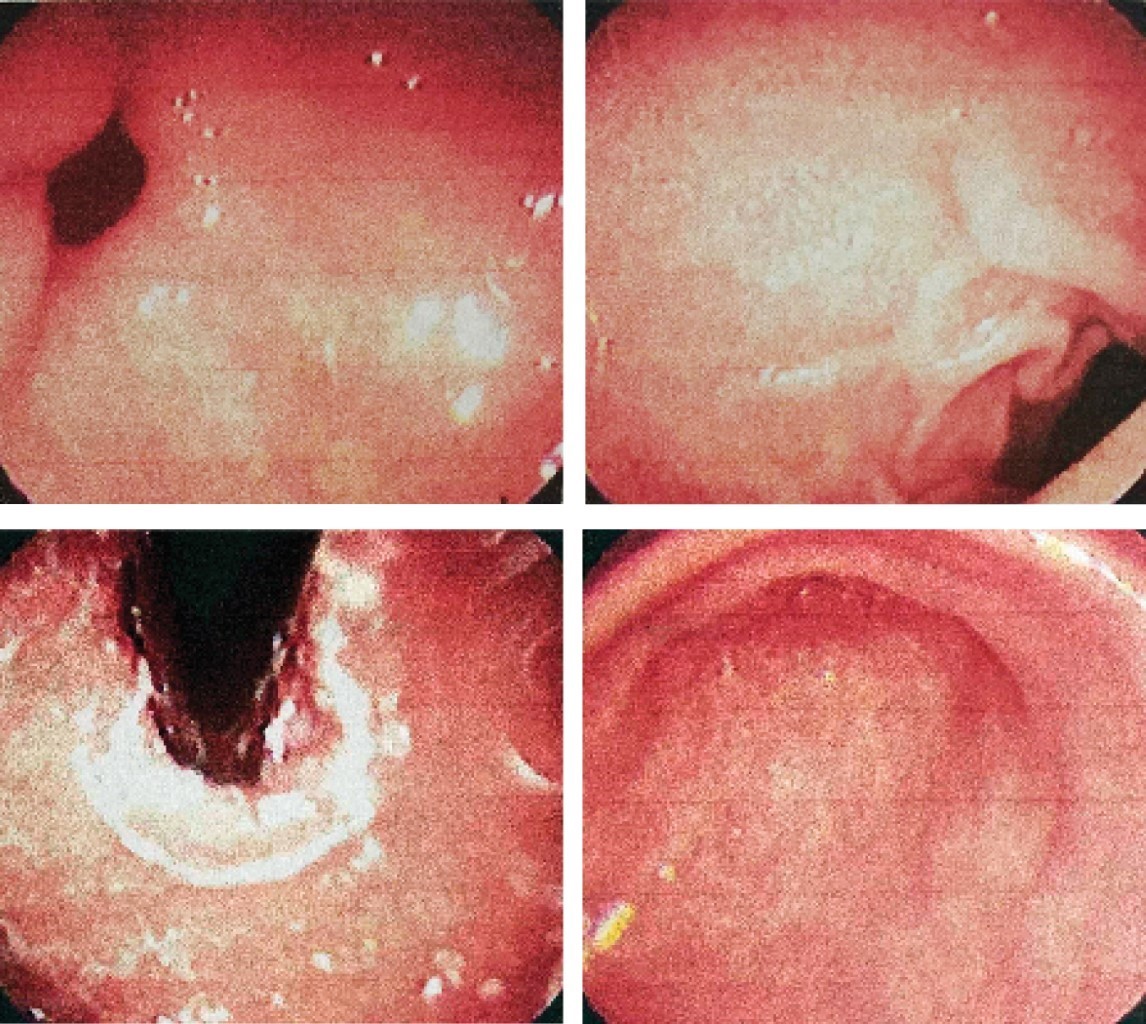

Paciente femenino de 66 años, no cuenta con antecedentes personales de importancia; manifiesta dolor en epigastrio, tipo urente, con irradiación retroesternal, refiere regurgitaciones y pirosis, sintomatología que mejora con el uso de inhibidor de bomba de protones y sucralfato, tratamiento que ha llevado de manera crónica, con eventos de remisiones y exacerbaciones, por lo que se inicia protocolo de estudio en sospecha de reflujo gastroesofágico. Se solicita endoscopia, la cual reporta probable dismotilidad esofágica tipo A de acalasia y gastritis leve antral (Figura 1). Con este resultado se solicita estudio contrastado y manometría.

Figura 1